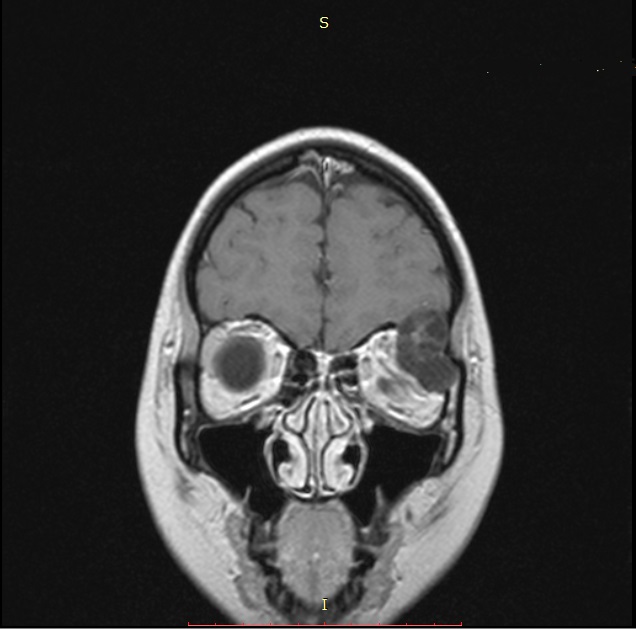

One of the cases involving the use of this technique was a teenager who underwent surgery at the end of 2020. The patient presented with proptosis (bulging eyes) and pain in the left superciliary area.

Examination and imaging revealed a left orbital mass spreading to the orbit walls and cranial cavity.

| MRI before surgery | 3D modeling before surgery The mass is marked in pink |